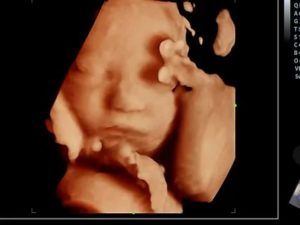

О замершей беременности позволяет узнать ультразвуковое исследование. Отсутствие сердцебиения плода однозначно говорит о том, что беременность прервалась. Одновременно с этим отмечается отставание плода в развитии на несколько недель. На ранних сроках о регрессе может свидетельствовать анэмбриония – «пустое» плодное яйцо.

- по УЗИ не определяется сердцебиение и шевеление плода. Может выявляться пустое плодное яйцо (анэмбриония)

Диагноз неразвивающейся беременности ставят при динамическом наблюдении за ростом матки, определяемом при влагалищном исследовании, а уточняют во время УЗИ.

При ультразвуковом исследовании можно абсолютно точно установить отсутствие сердцебиения эмбриона на сроках, когда оно должно определяться. Видимых проявлений (болей внизу живота, в пояснице, выделений из половых путей) в этом случае может не быть.